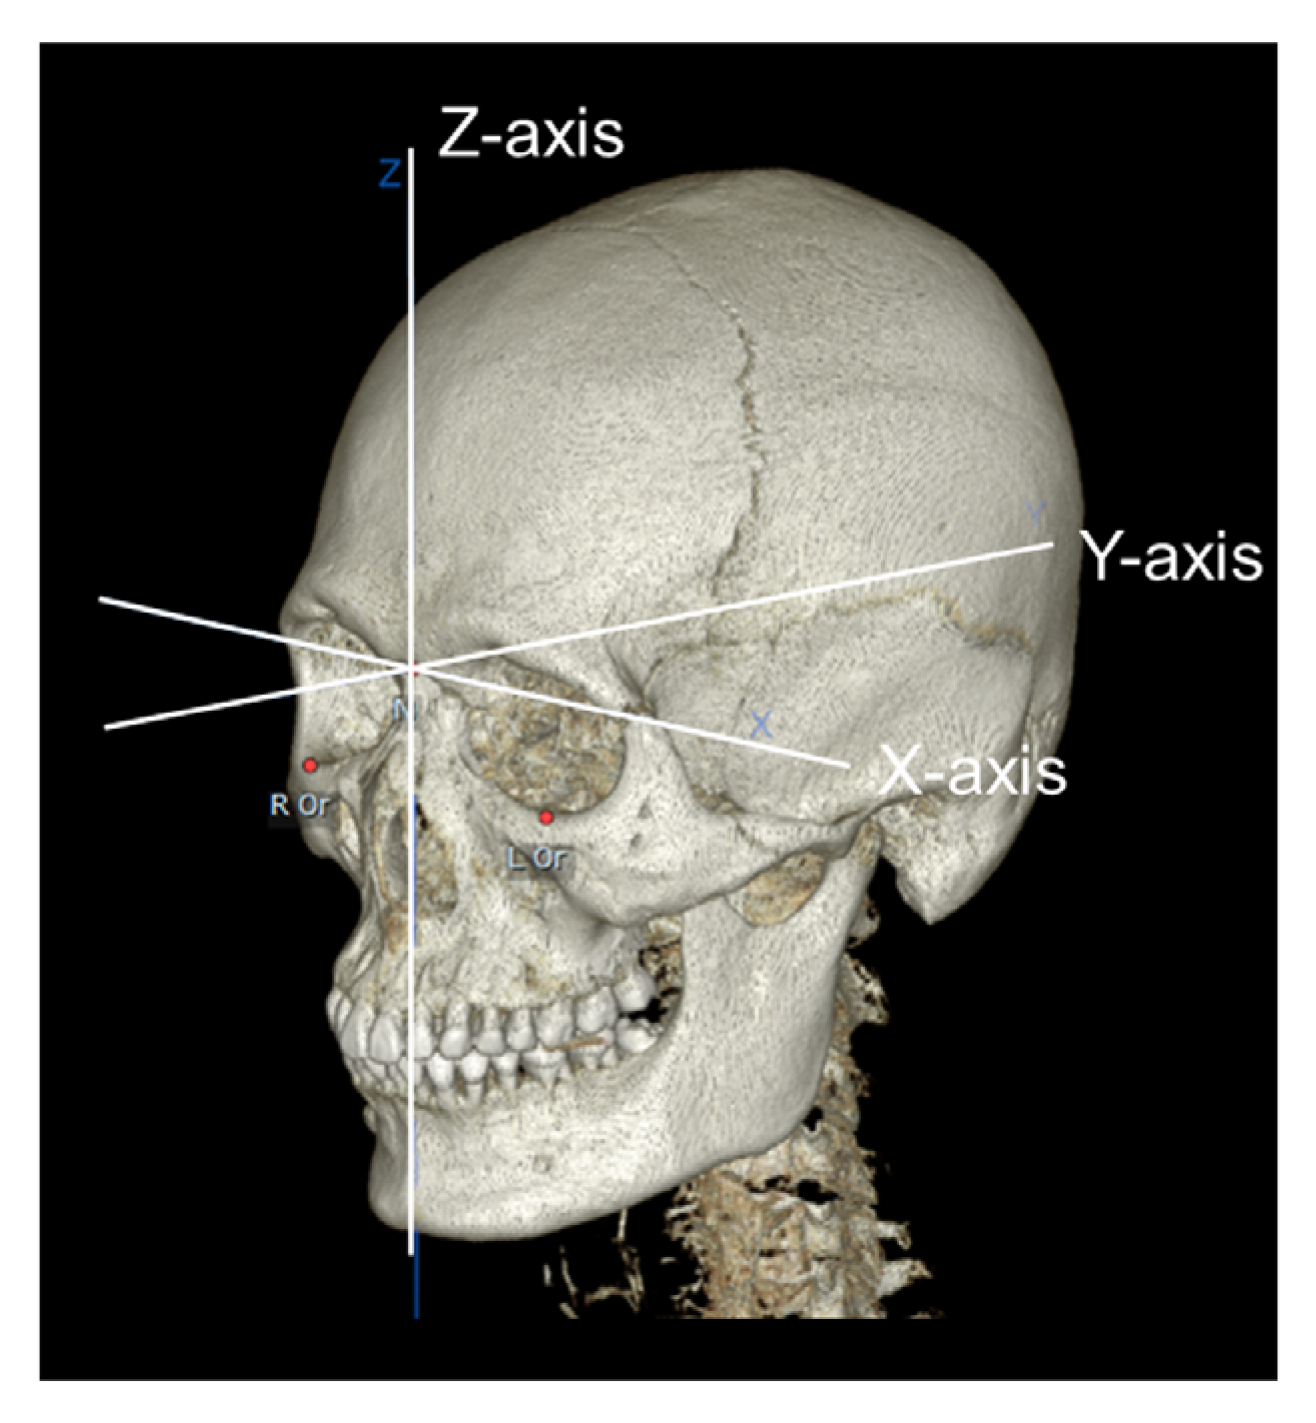

2. Materials and Methods

2.2. Data Acquisition

- Han, J.J.; Hwang, S.J. Three-dimensional analysis of postoperative returning movement of perioperative condylar displacement after bilateral sagittal split ramus osteotomy for mandibular setback with different fixation methods. J. Cranio-Maxillofac. Surg. 2015, 43, 1918–1925. [Google Scholar] [CrossRef]